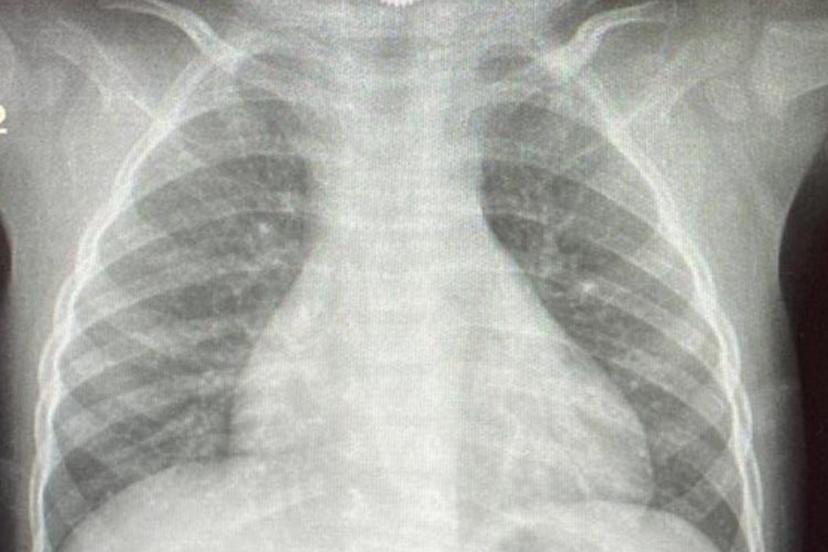

Çocuklarda sık karşılaşılan risklere değinen Özkaya "Günlük hayatta çocuklarda sık karşılaşılan yabancı cisim yutulması, kimyasal madde içilmesi ve solunum yollarına yabancı cisim kaçması önemli sağlık sorunları arasında yer almaktadır. Özellikle ilk üç yaşındaki çocuklar, yerde buldukları nesneleri ağızlarına götürme eğilimindedir. Madeni paralar, disk piller, iğneler ve küçük oyuncak parçaları çocuklar tarafından yutulabilmekte; bu maddeler yemek borusuna ya da solunum yollarına kaçabilmektedir. Bu tür durumlarda ailelerin olaya şahit olmaları hâlinde çocuğun ağzını kontrol etmeleri, yutma şüphesi varsa vakit kaybetmeden en yakın sağlık kuruluşuna başvurmaları gerekmektedir." dedi.

Solunum yollarına yabancı cisim kaçmasının da önemli bir risk olduğuna dikkat çeken Özkaya "Solunum yollarına yabancı cisim kaçması da günlük hayatta sık karşılaşılan ve hayati tehlike oluşturabilen durumlardan biridir. Özellikle üç yaşına kadar olan çocuklara çerez, fındık, fıstık, çekirdek gibi sert gıdaların verilmemesi gerekmektedir. Bu gıdalar solunum yollarına kaçarak ciddi nefes darlığına neden olabilmektedir. Böyle bir durumla karşılaşıldığında, mümkünse Heimlich manevrası uygulanmalı ve 112 Acil Servis eşliğinde en yakın sağlık kuruluşuna başvurulmalıdır. Bu tür vakaların operasyon gerektirebileceğine dikkat çekilerek, özellikle yemek borusunda kalan disk pillerin son derece tehlikeli olduğu vurgulanmaktadır. Disk piller, çocukta belirgin bir şikâyet olmasa bile kısa sürede yemek borusunda yanıklara ve delinmelere yol açabilmekte, hayati risk oluşturabilmektedir. Bu nedenle acil olarak ameliyathane ortamında çıkarılmaları gerekmektedir." şeklinde konuştu.